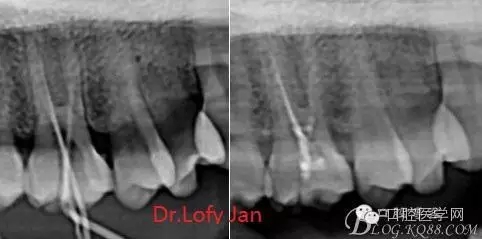

前言:自己做的一些曲面斷層片在未試尖根管治療中的病例整理,發(fā)現(xiàn)問題很多包括自身的,技術(shù)的,還有設(shè)備的問題,予以總結(jié)整理并期待進(jìn)一步提高。

根管治療術(shù)是牙體牙髓疾病治療中最復(fù)雜和最關(guān)鍵的治療項(xiàng)目。根管充填材料抵達(dá)根尖、并能嚴(yán)密堵塞根尖孔,是確保根管治療效果的關(guān)鍵指標(biāo)。為了保證根管充填到位,醫(yī)生需要在術(shù)前照牙片以了解牙根根管的數(shù)量、彎曲程度和長度,在術(shù)中有時(shí)需要插針照牙片來精確測量根管長度,術(shù)后必須照牙片以確定是否根管充填到位,如果欠填或超填,就需要重新充填、重新照牙片確認(rèn),直到根管充填到位。所以,在患者接受根管治療時(shí)有時(shí)會反復(fù)照牙片。

病例分析:曲面斷層片在x線輔助診斷與檢查中目前大多數(shù)文獻(xiàn)和著作都建議只能作為初診拍片檢查手段,不能作為終末疾病的確診與手術(shù)療效的評價(jià)指標(biāo),臨床大部分中小型門診都因?yàn)樵O(shè)備不齊全導(dǎo)致信息偏差很大。